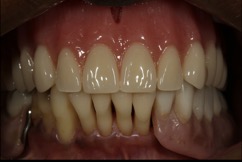

At the try-in appointment, the resin try-in denture confirmed good lip support and an esthetic incisor display, both when the patient was smiling and in repose. Even though no facebow was taken, the occlusal plane was not canted. Two small corrections were requested. The anatomic midline did not coincide precisely with the facial midline. Also because the denture was being created against a partially edentulous arch, the buccal cusp on the right first premolar needed to be extruded a bit to accommodate the plane of occlusion of the natural teeth. Both of these changes were incorporated into the final denture (Figure 15).

Fig. 15 The final Pala digital denture in place.

Figure 15